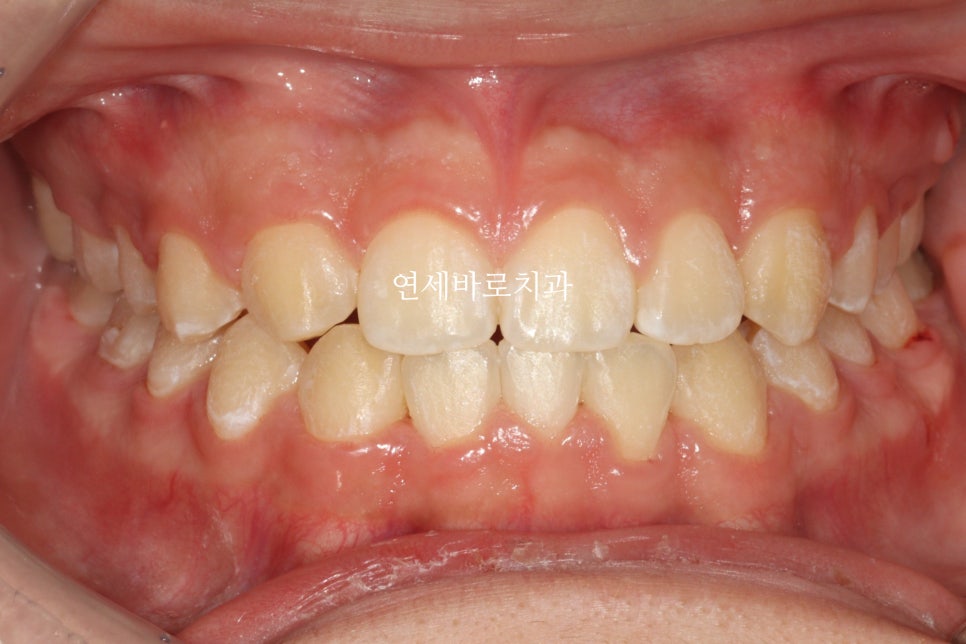

교정이 마무리된 지난주 모습입니다.

원래는 3 2 1 1 2 3 순으로 배열이 되어야 할 치아지만

가장 위를 보시면 번호가 빠진게 몇개 보이죠?

치아가 하나는 선천적으로 없었고, 아래 앞니 하나는 일부러 발치를 했습니다

이런식으로 눈속임 교정치료를 통해 치아를 배열했습니다

아마 일반인 분들은 일상생활속에서는 이상함을 느끼지 못할 정도라 생각합니다.